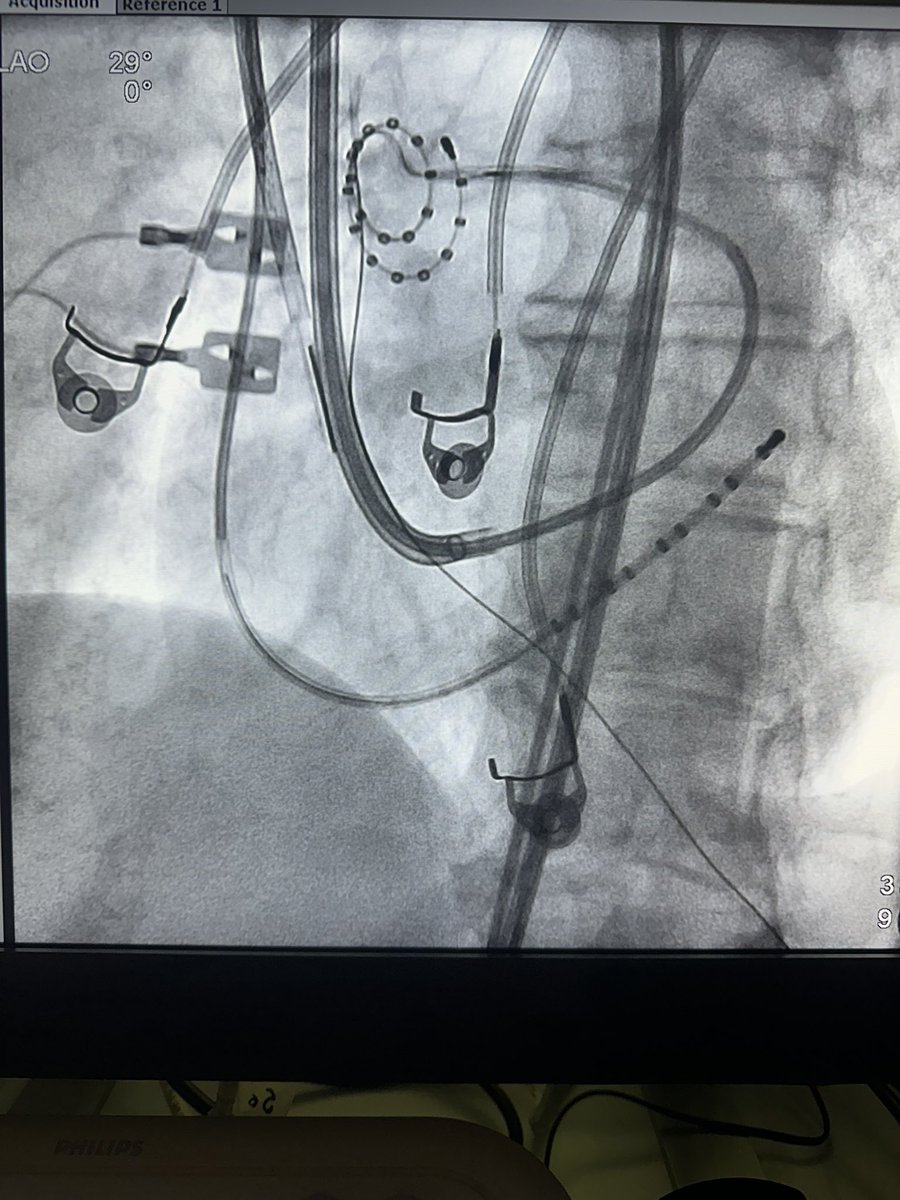

See you in the Valley of the Sun: 1-Day meeting, Fellows Abstract Competition, Live Cases from our ASC.